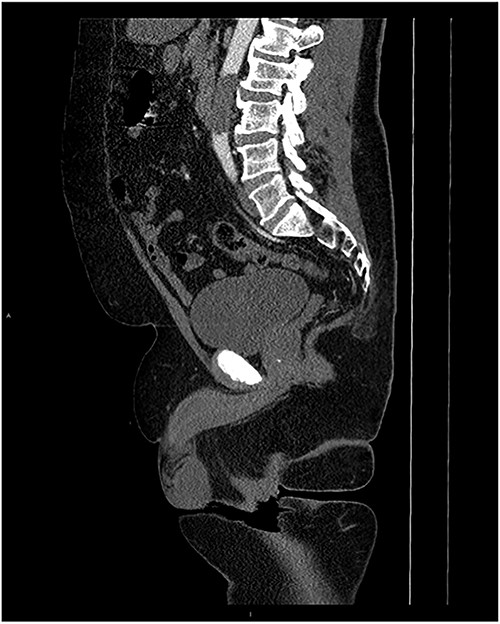

Upon admission to the ED, vital signs were stable, and an arterial duplex revealed diminished flow bilaterally in the common femoral arteries, superficial femoral artery and popliteal arteries, suspicious for aortoiliac disease. A computed tomography angiogram (CTA) with runoff was then conducted, which showed a near-complete occlusion of the infrarenal abdominal aorta below the level of the inferior mesenteric artery (Figs 1 and 2). The patient was promptly seen by vascular surgery and planned for an open aortic thrombectomy.

MRI Sagittal with contrast with occlusion of the abdominal aorta.